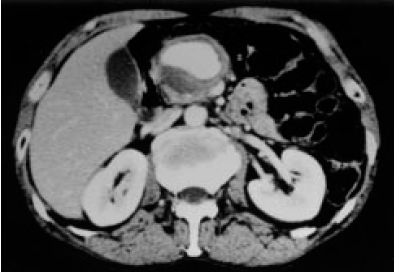

- Kontrastlı KT və ya MRT standart müayinədir, şişi və yayılma dərəcəsini müəyyənləşdirilməsində önəmlidir.

- Görüntüləmdə: erkən arterial fazada contrast tutan və venoz fazada yuyulan, MRT-də hipointens, ətraf toxumalara invaziv, böyüməyə meylli, baş nahiyyəsində yerləşərək xoledoxu və pankreatik axacağı genişləndirən (“iki axacaq simptomu”) törəmə

- Kontrastlı KT/MRT (5 mm-lik kəsiklərlə aparılan kontrastlı KT/MRT 50 – 60% həssaslıq göstərir.